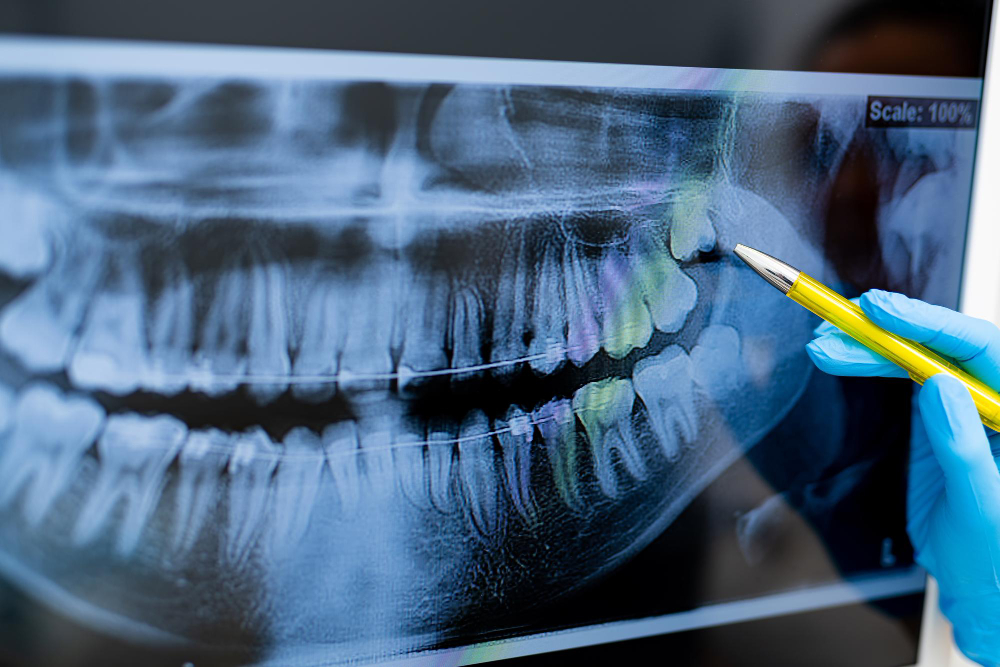

Dental Radiographs (X-Rays)

Dental radiographs (x-rays) are essential, preventative, diagnostic tools that provide valuable information not visible during a regular dental exam. Dentists and dental hygienists use this information to safely and accurately detect hidden dental abnormalities and complete an accurate treatment plan. Without x-rays, problem areas may go undetected.

Request an AppointmentDental x-rays may reveal:

- Abscesses or cysts

- Bone loss

- Cancerous and non-cancerous tumors

- Decay between the teeth

- Developmental abnormalities

- Poor tooth and root positions

- Problems inside a tooth or below the gum line